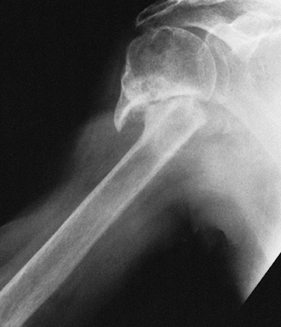

likely (Fig. 101.7)

Figure 101.7.

A four-part fracture dislocation. The humeral head is devoid of

soft-tissue attachment, late collapse is likely, and prosthetic

replacement is the surgical treatment of choice. -